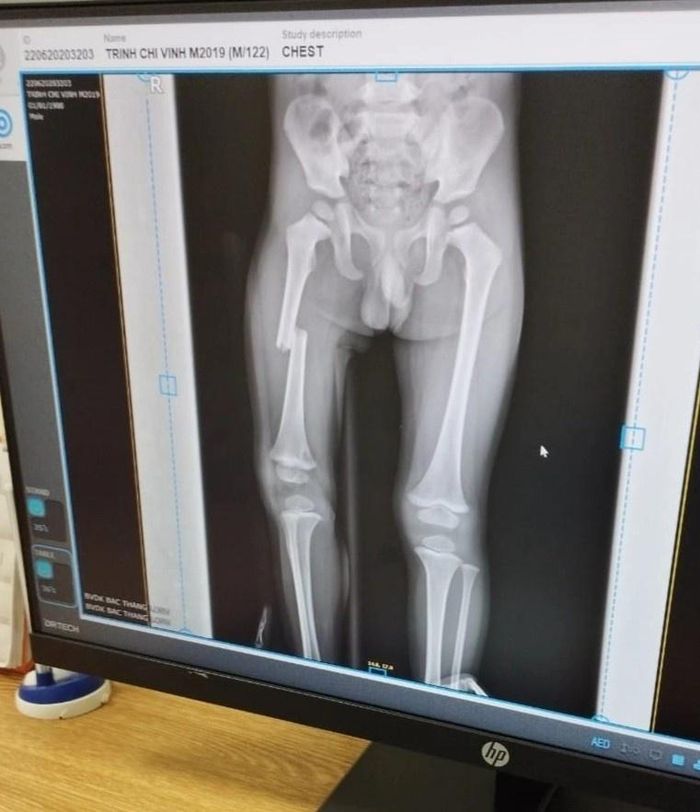

Ảnh chụp X-quang xương chân cháu bé. Ảnh: Gia đình cung cấp.

Chiều 23/9, lãnh đạo Công an huyện Lục Ngạn, tỉnh Bắc Giang, cho biết đơn vị đang điều tra, xác minh vụ một bé trai bị mẹ đạp gãy xương đùi xảy ra tại xã Quý Sơn. Cơ quan công an đã mời những người liên quan đến làm việc, trong đó có mẹ của bé trai. Về tình trạng sức khỏe của cháu bé, lãnh đạo công an huyện cho biết nạn nhân đã bình phục, có thể đi học bình thường.

Theo anh N. cũng cho biết sự việc bắt nguồn từ việc cháu bé cầm chìa khóa của mẹ để chơi. Sau khi tìm không thấy, người phụ nữ bực tức, dùng chân đạp liên tục vào đùi con trai. Sự việc được camera an ninh ghi lại.